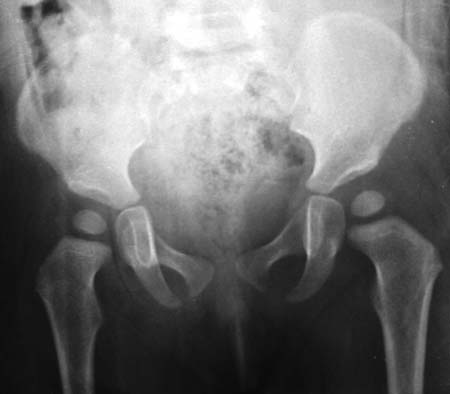

标题: PED0495:髋脱位治疗复查对比

第一副图象是治疗前的 第二副图象是治疗后的 前后时间相差6个月